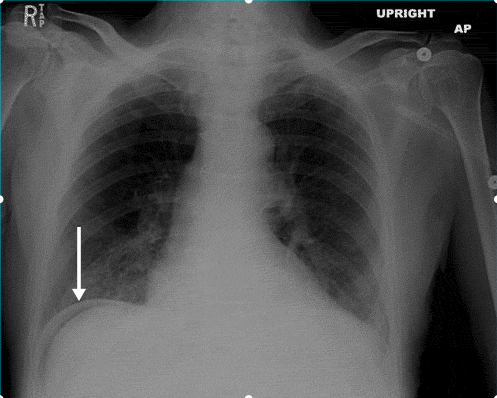

That upright X-ray is a classic "spot diagnosis" for perforation. When you see that crescent of air under the diaphragm, it's a surgical emergency.

| Key Imaging | CT (Adults), US (Kids/Pregnancy) | X-ray (Air-fluid levels) | Upright CXR (Free air) |